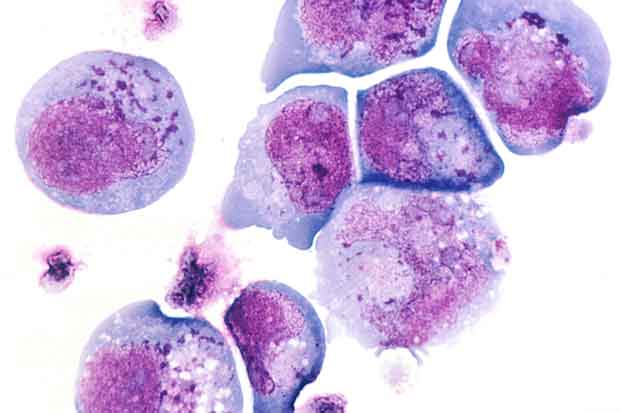

L’herpesvirus umano 6 (HHV-6) – l’agente eziologico dell “sesta malattia”, una patologia esantematica infantile solitamente benigna – infetta quasi il 100 per cento delle persone fin dalla prima infanzia, restando nell’organismo in modo permanente. Ora però un gruppo di ricercatori dell’Università della South Florida diretti da Peter Medveczky ha scoperto che in una piccola percentuale di persone riesce a integrare il proprio DNA nei cromosomi umani.

Nel corso dello studio, descritto in un articolo pubblicato sui Proceedings of the National Academy of Sciences, i ricercatori hanno anche confermato il sospetto, avanzato anni fa in seguito ad altre ricerche, che l’HHV-6 è in grado di infettare spermatozoi e cellule uovo. Di conseguenza, circa l’uno per cento della popolazione (la stima è stata condotta sulla popolazione statunitense) nasce con il DNA del virus presente in tutte le cellule del corpo. Di fatto HHV-6 è il primo virus che si è dimostrato in grado di trasmettersi in modo funzionale attraverso la linea germinale umana.

Dallo studio è risultato che il sito di inserzione del virus è all’interno dei telomeri, strutture alle estremità dei cromosomi che hanno un ruolo centrale nella regolazione della divisione cellulare e quindi dei processi di invecchiamento e dello sviluppo dei tumori.